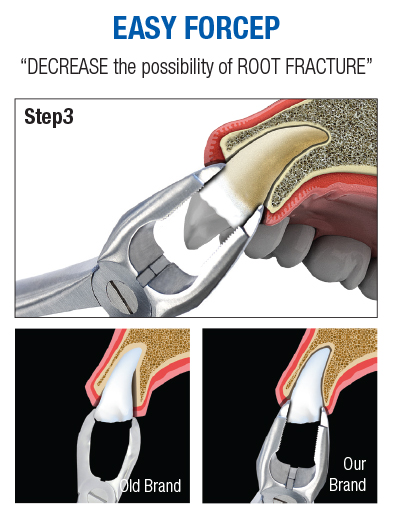

EASY FORCEP delivers force by grasping more apical portion than previous instruments, decreasing the possibility of root fracture significantly during extraction.